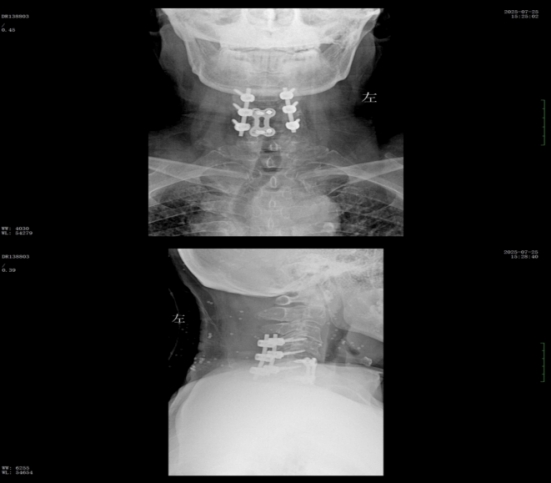

經(jīng)過精準(zhǔn)手術(shù)和術(shù)后系統(tǒng)的康復(fù)治療,患者神經(jīng)功能得到明顯恢復(fù),四肢肌力及感覺逐步改善,術(shù)后肌力達(dá)到IV級(jí)左右。復(fù)查X線顯示內(nèi)固定位置理想,患者非常滿意。出院之際,患者及家屬對(duì)衡陽市中心醫(yī)院的醫(yī)療技術(shù)、護(hù)理服務(wù)及醫(yī)聯(lián)體轉(zhuǎn)診效率均給予高度評(píng)價(jià)。

術(shù)后x線內(nèi)固定位置理想